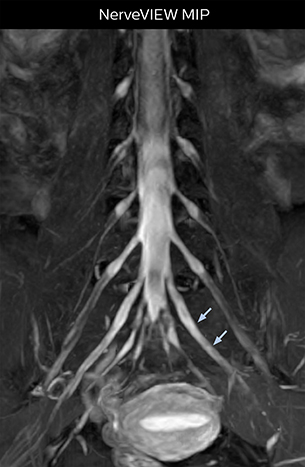

Northern Fukushima Medical Center (NFMC) Imaging Center uses the 3D NerveVIEW sequence for performing MR neurography, particularly in patients with pain and weakness in the lower limb. “It is included in about 20% of the approximately 150 lumbar spine MRI exams each month at NFMC, and can help us to determine if structures are impinging on the nerves,” says Hajime Tanji, RT, MRI technologist at NFMC.

“In such case, we would then browse through axial T2-weighted MR images slice by slice and mentally reconstruct the actual situation based on both radiculography and MRI. Fortunately, NerveVIEW can now very well show nerve courses and presence of nerve compression or edema in one single image series.” “We have often seen NerveVIEW directly depict details of the nerve compression that were not observed by radiculography. Therefore, we think that with NerveVIEW we can reduce the number of invasive examinations, especially for some patients with lumbar plexus symptoms.”

“The intra-luminal signal of veins, especially around the intervertebral space, can be suppressed well with NerveVIEW. As a result, we can easily observe the detailed nerve structure around the posterior ganglion,” he says. “This is why we use 3D NerveVIEW for intraforaminal stenosis and extraforaminal stenosis/herniation (lateral disc herniation). On the other hand, if herniation is suspected to exist inside the dorsal root ganglion (DRG), balanced TFE or ProSet-FFE is applied. NerveVIEW is not suitable for evaluating the median type of herniation.” The SE-EPI DWI-based method for MR neurography works well for large FOV exams like whole-body MRI, but focal examination of nerves is often limited by the attainable spatial resolution (both inplane and slice direction) and geometric distortion. “3D NerveVIEW achieves higher in-plane resolution – close to our other routine spine sequences – and the source images can be used instead of adding a fat-suppressed T2-weighted sequence,” Tanji says.

According to Tanji, methods such as ProSet FFE, STIR or 3D VISTA are anatomically nonselective because background signals, for instance from blood vessels, often interfere with nerves, which hampers evaluation of details, especially at the peripheral side of the nerves.

“For both brachial and lumbar plexus, we are currently using a 230 mm FOV and voxels of about 1 x 1 x 2 mm acquired (1 x 1 x 1 mm reconstructed). This provides us a good representation of the nerves, even though this FOV is relatively small. Regarding the inplane resolution, we hope to be able to bring that down to 0.7 mm, similar to our typical 2D multislice T2W images,” says Tanji.

Implementing NerveVIEW without lengthening exam time “The source images of NerveVIEW exhibit a contrast similar to STIR or fat-suppressed T2-weighted images. So, in our neurography exams we are replacing the 2D T2-weighted coronal sequence with 3D NerveVIEW. With this, we add a lot of useful information without adding scan time. This is important for patients with severe lower extremity symptoms, as they often find it difficult to maintain still during the whole MRI examination, so the exam should be as short as possible.” “We have currently implemented 3D NerveVIEW on our Achieva 3.0T dStream MRI system only. Because the 3D NerveVIEW method is based on a background signal suppression technique, we decided to use the high SNR of our 3.0T MRI system for obtaining the best possible visualization of peripheral nerves,” says Tanji. “Where NerveVIEW of the lumbar plexus is currently used as a subroutine scan for patients with strong lower limb symptoms, its use for visualization of the brachial plexus, is currently limited to special cases such as schwannomas and neuritis, usually only 1 or 2 cases per month.”